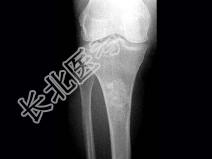

- 单项选择题女,年龄47岁, 膝关节疼痛6月余,曾服用泼尼松(服用时间5个月), 有骨性关节炎史,结合图像, 最可能诊断是 ( )

A、慢性化脓性骨髓炎

B、骨梗死

C、恶性骨肿瘤

D、内生软骨瘤

E、骨纤维结构不良